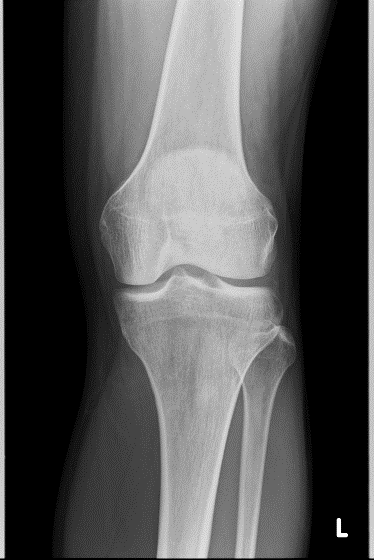

一般撮影

一般撮影は、X線を使用し胸部撮影(肺野・縦隔などの診断)、腹部撮影(腹部臓器、ガス像などの診断)、骨・関節の撮影(関節の状態、骨折などの診断)など全身の撮影を行っています。

当院では、画像処理装置として富士フィルム製の装置(FPD:フラットパネルディテクタ)を使用し、診断に適した画像情報を提供しています。一般撮影室は2つあり、検査内容に合わせて装置を使い分けています。